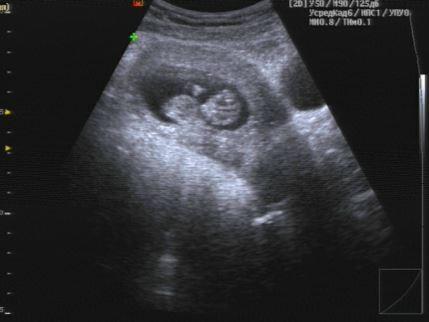

Встала на учет + 1 скрининг пройден (фото) ! 12 недель ровно

Изменения и болезни во время БНу вот, наконец-то я снова увидела свою бусинку!😍 Заряд эмоций теперь на весь день 🤗 Лялечка наша очень активна, шевелила и ручками, и ножками, так забавно за этим наблюдать! Столько волнения было перед осмотром, но врач почти сразу начал улыбаться и позвал мужа, чтоб показать ему. Тут то я и расслабилась.😁 Пол пока рано говорить, но сказали если мальчик - то через две недели уже будет заметно. А вообще точно сказать можно будет ближе к 20 недели.

По параметрам вроде все хорошо, КТР - 50мм, ЧС - 166 уд/мин, размер матки 109х88х88.

УЗИ смотрели только по животу, вагинально на этот раз датчик не вводили, все итак довольно хорошо было видно.